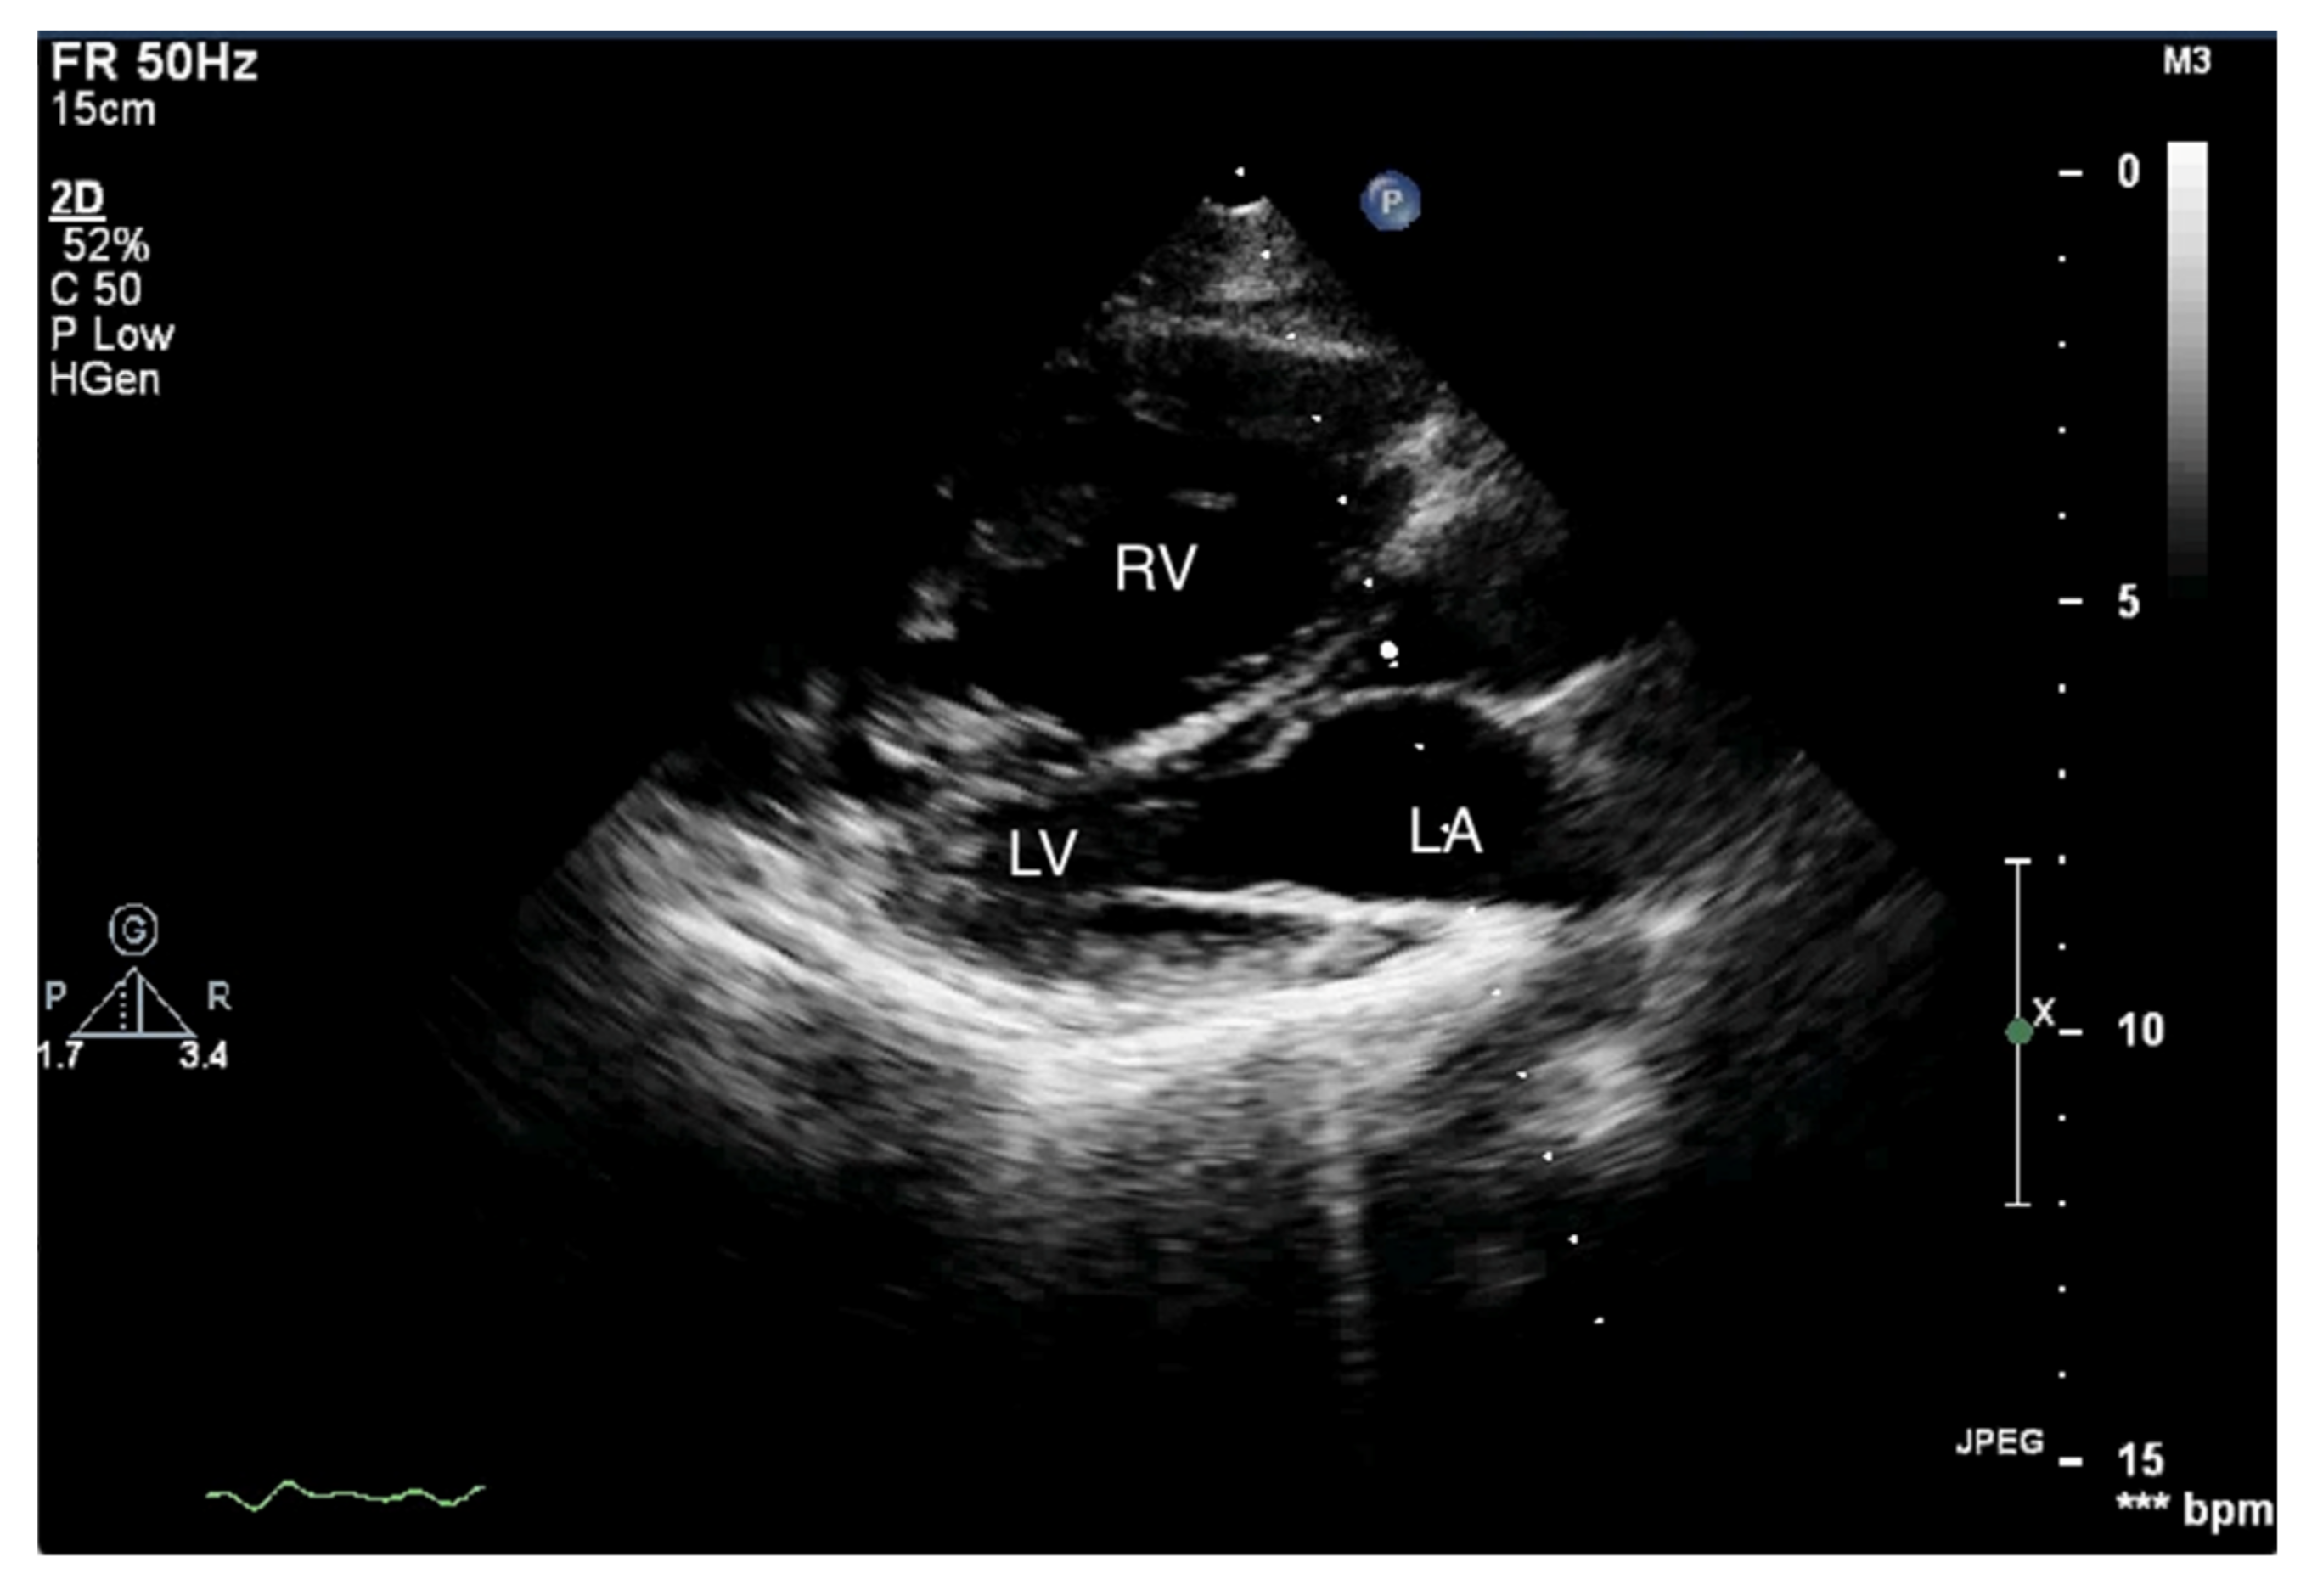

Figure 1.

Enlarged right ventricle. Two-dimensional transthoracic echocardiography (2D-TTE), parasternal long-axis view (PLAX). RV: right ventricle, LV: left ventricle, LA: left atrium.